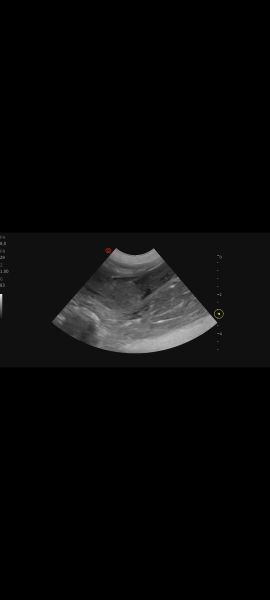

Hi, my vet performed an ultrasound on 7 year old lab mix because of an UTI .She said her bladder walls look thickened and spongy. She's concerned. Can you tell anything? I'll try to add more pics under commentsScreenshot_20251230_161511_PhotosScreenshot_20251230_161500_PhotosScreenshot_20251230_161447_Photos